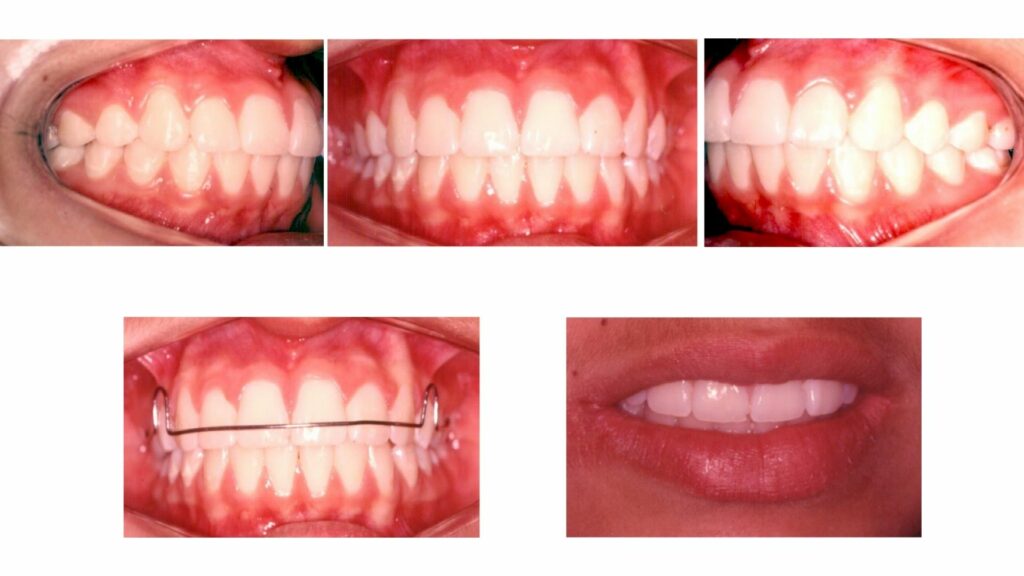

Resultados mais estáveis e duradouros.

Melhor estética e harmonia facial.

Unificação dos conceitos de saúde, estética e função.